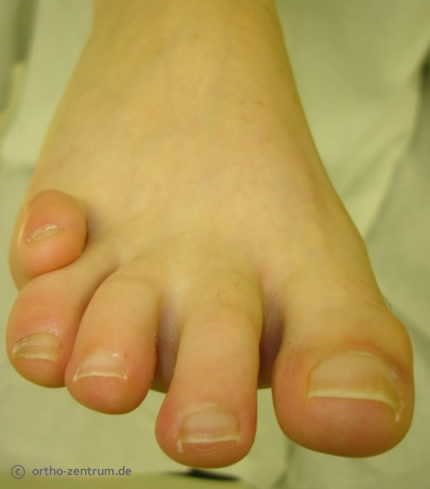

Hammerzehe und Krallenzehe

Die häufigsten Kleinzehendeformitäten sind die Hammerzehe und die Krallenzehe.

Der Hauptunterschied zwischen beiden besteht darin, dass die Krallenzehe im Gegensatz zur Hammerzehe mit der Zehenspitze nicht mehr den Boden berührt. Oftmals sind die beiden der Großzehe benachbarten Zehen betroffen, vorwiegend dann, wenn bedingt durch eine Hallux valgus-Fehlstellung der zweiten Zehe wenig Platz hat. Beschwerden entstehen insbesondere in engem Schuhwerk, was sich als gerötete Schwielen an der Oberseite bemerkbar macht. Auch hier werden verschiedene operative Maßnahmen erfolgreich angewendet. Bei der Hohmann-Operation wird ein kleiner Teil des Knochens entfernt und die Zehe wieder gerade ausgerichtet. Ein Sehnentransfer kann bei flexiblen Verhältnissen durchgeführt werden.